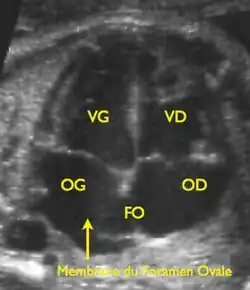

Le foramen ovale est un passage en forme de fente « en chicane » entre les deux constituants principaux de la cloison inter-auriculaire, le septum primum du côté gauche et le septum secundum du côté droit. Il fait communiquer les deux atriums. Il tend à être fermé par une membrane (« la membrane du foramen ovale ») qui n'est maintenue en position ouverte que par la différence de pression régnant dans les atriums.

La circulation pulmonaire du nouveau-né devient parfaitement fonctionnelle et assure 100 % du débit cardiaque (contre 7 % seulement avant la naissance). Le retour de cette circulation pulmonaire, par les veines pulmonaires qui s'abouchent dans l'atrium gauche, provoque une élévation des pressions régnant dans cette cavité, lesquelles finissent par dépasser celles de l'atrium droit. La membrane du foramen ovale tend alors à être plaquée contre la cloison interauriculaire et à interdire tout passage significatif de sang par cette communication.

Dans les premières semaines de vie, cette fermeture n'est que fonctionnelle et liée à la différence de pression entre les atriums. On pourrait alors comparer le foramen ovale à une porte qui serait simplement poussée mais sans que la serrure soit enclenchée, un simple courant d'air suffisant à la rouvrir. Normalement, après quelques mois, se constituent des adhérences qui maintiennent définitivement fermée cette communication.